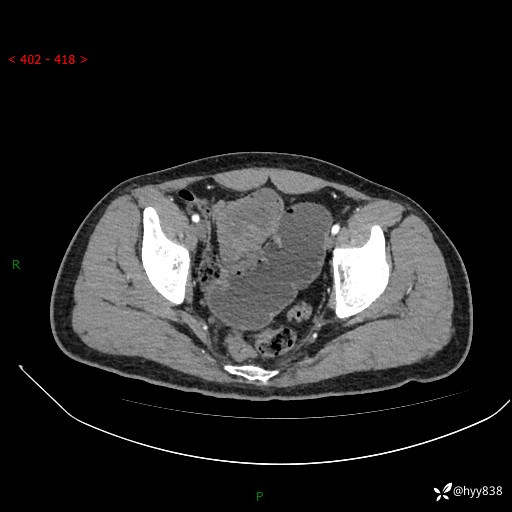

年轻男性,腹痛5月余。除了肠梗阻,你还能看到什么---结果公布~

现病史:患者于5月前无明显诱因开始出现腹痛,上明显,为间断性胀痛不适,无畏寒发热,无心慌气促等特殊不适,遂来我院。我院门诊遂以“腹痛原因待查”收入我科。 起病以来,患者精神、饮食、睡眠欠佳,大小便正常。体力体重无明显变化。

腹部CT增强扫描(动脉期+静脉期)